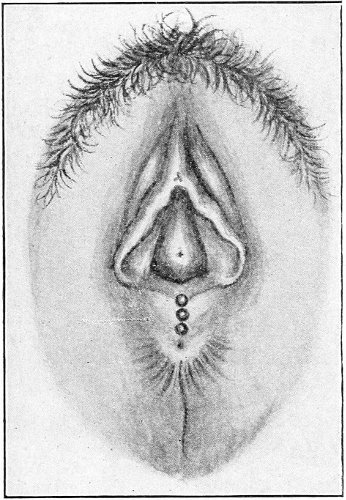

Fig. 16.—Appearance of the external genitals in a woman with gonorrhea: G. m., gonorrheal macula situated at the base of a vaginal caruncle.

Suppuration of the duct may be demonstrated by pressing over the course of the duct, when a drop of pus will escape from the opening. In such cases the orifice of the duct is usually surrounded by a red areola, resembling a flea-bite, which has been called the gonorrheal macula (Fig. 16). This macula persists long after all other traces of inflammation about the vulva and vagina have disappeared, and after all frank suppuration in the duct has subsided. Its presence indicates at least the probability of previous gonorrheal infection.

Suppuration of the vulvo-vaginal gland is accompanied by marked swelling and peripheral edema. The swelling may extend to the anus, and is of characteristic shape (Fig. 17). The pain is always severe. Fluctuation is first apparent on the inner surface of the labium majus. If the condition is not treated, one or more fistulous openings appear below the orifice of the duct, and the pus is discharged. The condition then becomes chronic. The fistulous openings persist. Acute inflammation disappears from the gland, leaving it in a condition of hypertrophic induration. A thin, milky or greenish, purulent fluid may be pressed out of the duct or the fistulous openings. Infection from this discharge may be communicated to man, or may ascend the genital 40 tract, producing inflammation of the endometrium or of the Fallopian tubes.

Fig. 17.—Abscess of right vulvo-vaginal gland.